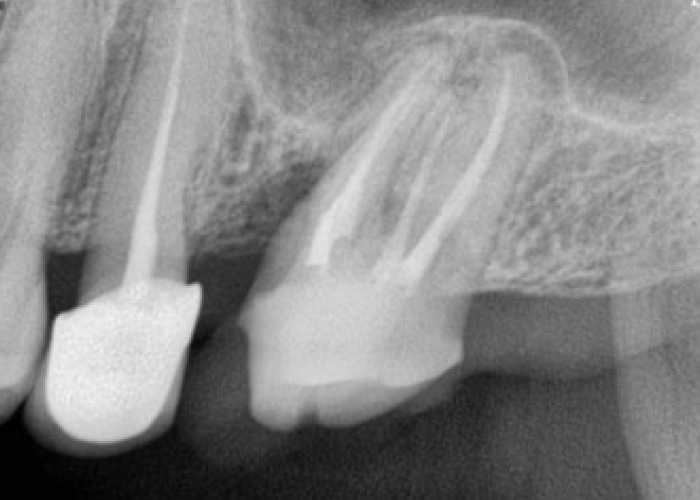

신경치료 전후 사례

• 치료 전

치료 후